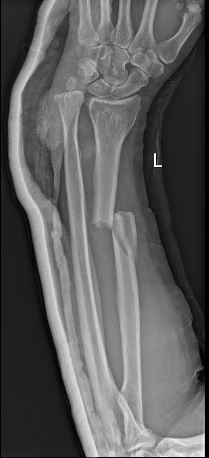

Xrays

Before surgery After Surgery